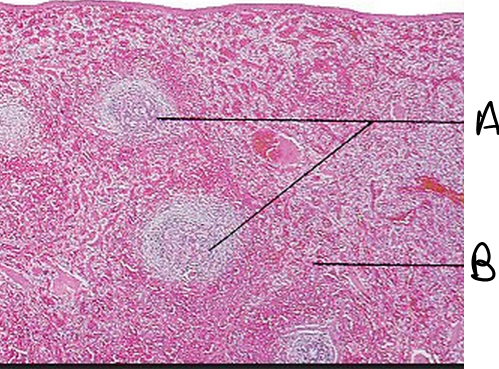

Q

What is this lymphatic organ? What are the structures labled A and B? What are their primary functions

A

Spleen

A= White Pulp (lymphocytes, where immune responses occur)

B= Red Pulp (stores RBC)